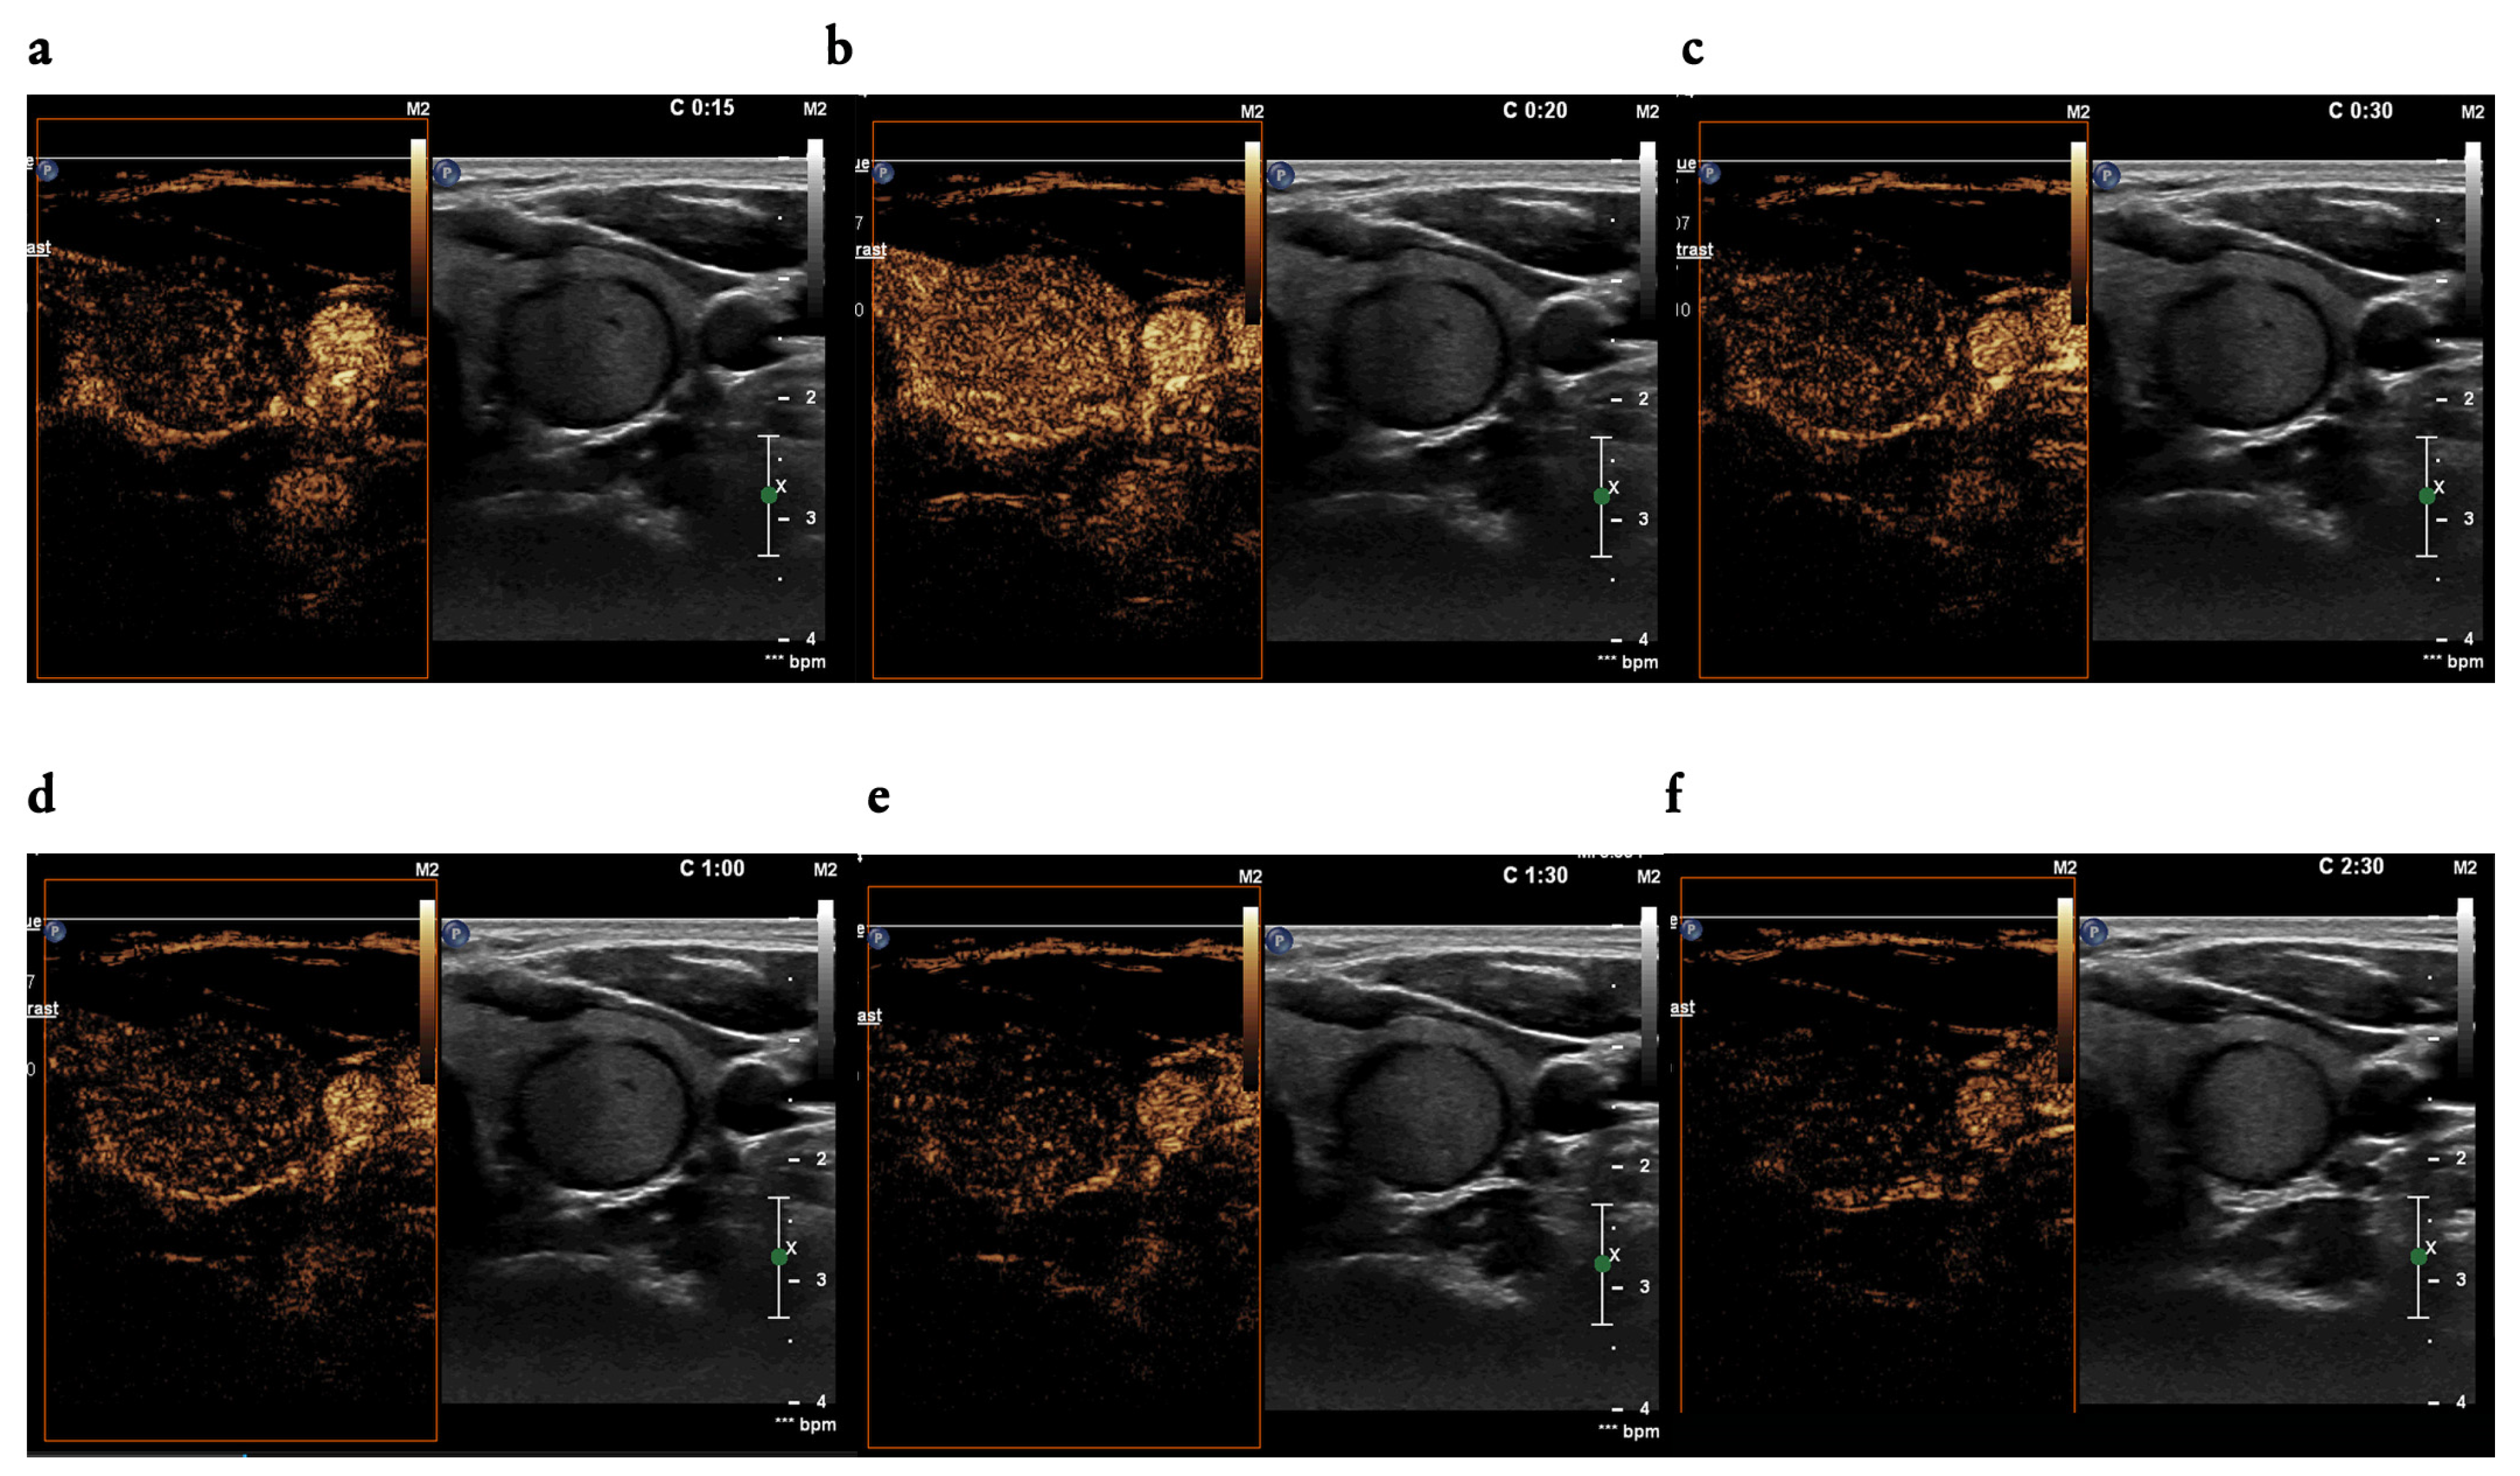

3.3. CEUS Findings

4.4. The Utility of CEUS Patterns Assessed in the Study in Line with the Literature Review—Malignant Nodules

4.5. The Utility of CEUS Patterns Assessed in the Study in Line with the Literature Review—Benign Nodules